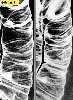

A case of intestinal amyloidosis which showed a diffuse coarse mucosa.

Tokyo Pref., Cooperative study between National Cancer Center and Kyushu Cancer Center

Inflammatory or ulcerative disease / lesions/Amyloidosis